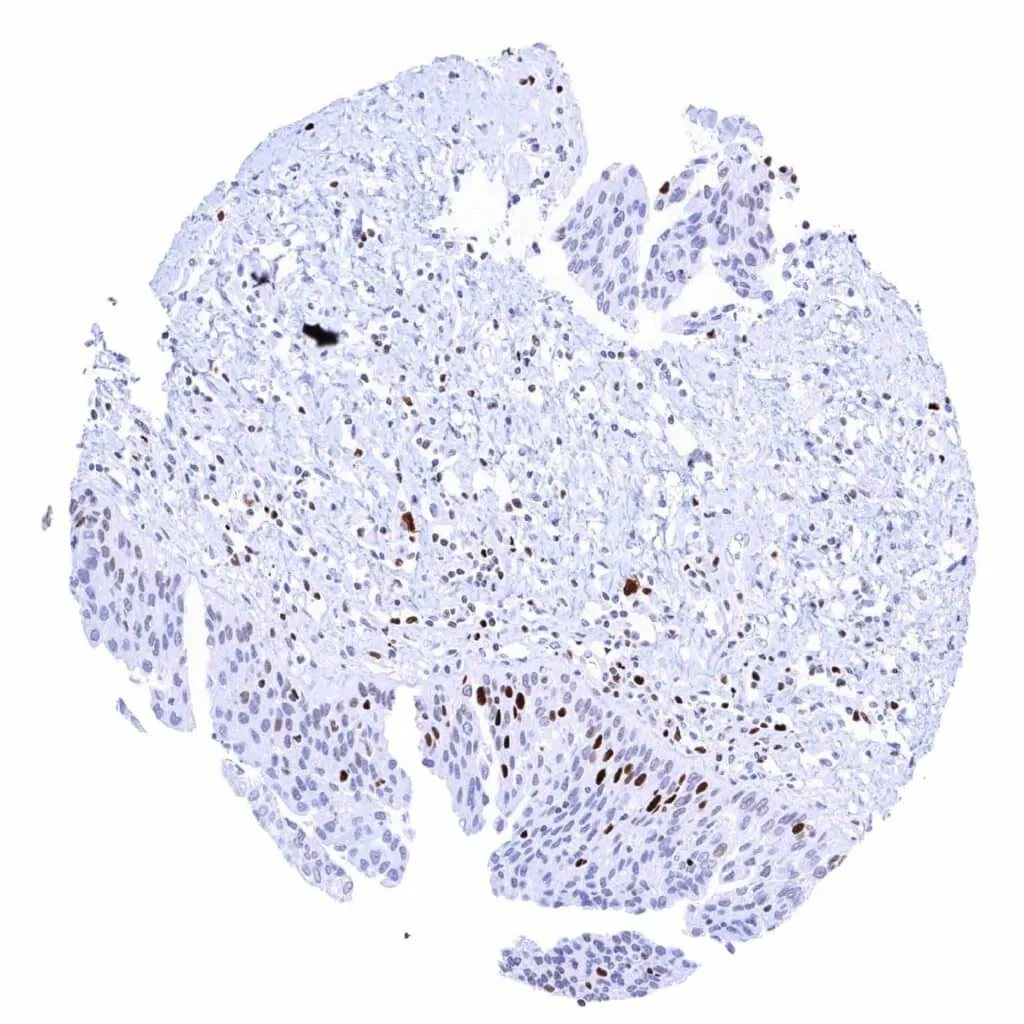

Lymph node – Many lymphocytes are MCM2 positive. Strongest MCM2 staining occurs in most cells of germinal centres and in scattered individual cells of the interfollicular zone